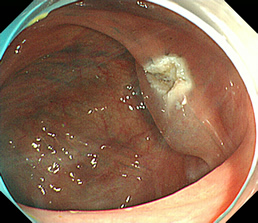

見つかったポリープ

ポリープに色素を吹きかけた状態

粘膜下層に生理食塩水を注入し、盛り上げた状態

高周波電流で粘膜下切除を行った状態

切除後クリップにて止血胃瘻造設術